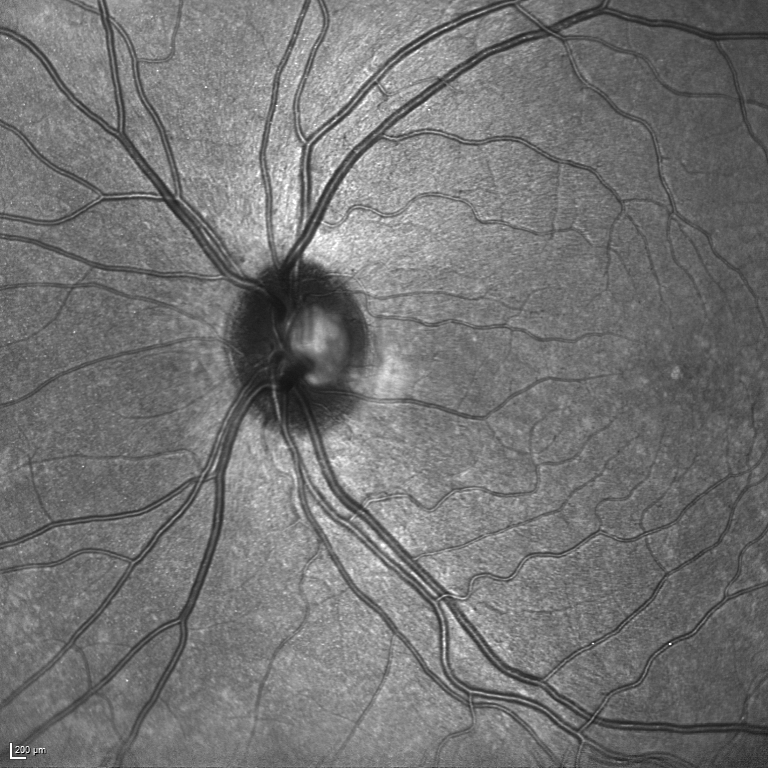

Recently there has been a substantial increase in the utilization of single wavelength confocal imaging that only captures reflected light passing through a pinhole, which will allow capturing high quality, high contrast fundus images. The images in our RAVIR dataset were captured using infrared (815nm) Scanning Laser Ophthalmoscopy (SLO), which in addition to having higher quality and contrast, is more convenient for the patient and is less affected by opacities in optical media and pupil size. This imaging modality is also commonly used in ophthalmology clinics. The RAVIR dataset consists of 46 IR retinal images from the UCLA Stein Eye Institute imaging database, divided into train and test sets of 26 and 20 images, respectively. We used 4 images from the 26 test images as our validation set. The images were captured using a Heidelberg Spectralis camera with a FOV. They are sized at pixels and compressed in the Portable Network Graphics (PNG) format. Each pixel in the images has a reference length of 12.5 microns. Table I compares our RAVIR dataset against other retinal vessel segmentation datasets.

Manual pixel-wise annotations were performed and verified by our experienced retinal image analysis specialist. Per-pixel labels were applied to all vessel regions that could accurately be identified as artery or vein. Vessels were labeled over the ONH in those images where the arteries and veins could be resolved. However, for images in which the veins and arteries over the ONH were indistinguishable, the ONH region was blocked for masking.